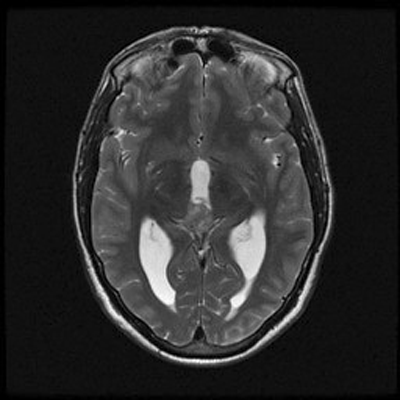

An MRI of the brain with and without contrast revealed a 2.6 x 1.3 x 1.6 cm  (AP x CC X W) heterogenous lesion within the region of the pineal gland and projecting into the third ventricle. The lesion had both solid and cystic components and demonstrated heterogenous enhancement on T1-weighed images. The enhancement is located medial to the veins of Rosenthal, inferior to the cerebral veins, and posterior to the vein of Galen. The mass is isointense to the cortex on T2-weighed images. No significant midline shift or significant edema was observed. The ventricular system was prominent in size, consistent with mild hydrocephalus. Basilar cisterns were preserved and normal cerebrovascular flow-voids were seen.  No abnormalities of the cerebellar or cerebral parenchyma, the brainstem or the cervical spinal cord were observed. Dural venous sinuses and meninges were unremarkable. Regions of the orbit and sella were unremarkable. Paranasal sinuses demonstrated paranasal sinus disease of the bilateral maxillary and left ethmoidal sinuses.

T2